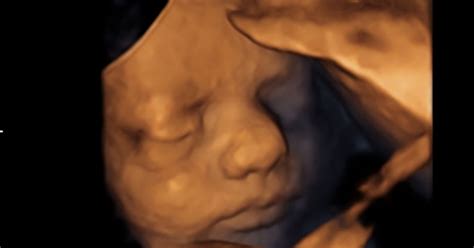

V 33. tednu nosečnosti je vaš dojenček že skoraj povsem razvit. Tehta okrog 1,7 kilograma in meri približno 44 centimetrov od glave do pet. Njegova koža je vse manj nagubana in njegov obraz je vse bolj okrogel, saj se pod njo nalaga vse več maščobnega tkiva, ki mu bo pomagalo pri regulaciji telesne temperature po rojstvu. V tem tednu se otrokovi možgani zelo hitro razvijajo, kar se odraža v povečanju njegove glave. Med lobanjskimi kostmi, ki so še vedno mehke in prilagodljive, nastanejo mehka mesta, znana kot fontanele ali mečave. Te omogočajo, da se lobanjske kosti med porodom upognejo, kar olajša prehod skozi porodni kanal in zagotavlja prostor za nadaljnjo rast možganov po rojstvu.